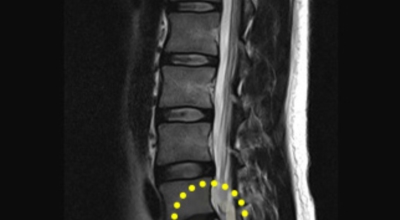

디스크는 일어선 상태에서는 중력을 받아 납작해져서 바깥쪽으로 약간 볼록한 형태가 된다고 합니다. 디스크는 그 특수한 구조 때문에 웬만한 힘이 가해져도 효율적으로 쿠션 역할을 할 수 있겠습니다. 그러나 급작스럽게 무거운 물건을 들어 올리거나, 부자연스러운 자세를 오랜 시간 취하면 디스크에 무리한 힘이 가해지면서 디스크가 밖으로 돌출이 되게 돼요. 심한 경우 디스크를 감싼 막이 터지면서 그 안에 있는 수핵이 튀어나오게 돼요.

디스크는 대개 후방이나 후외방으로 돌출되는데 이때 바로 곁에 있는 신경을 누르게 된다고 합니다. 돌출된 디스크는 척추의 어느 부위에나 일어날 수 있어요. 목에 생기면 '목 디스크', 등에 생기면 '등 디스크', 허리에 생기면 '허리 디스크'라고 부른다고 합니다.

이와 같이 디스크가 돌출되어 신경을 눌러 요통 또는 다리가 아프고 저린 증상을 유발하는 병을 '추간판 탈출증' 및 '디스크 탈출증'이라고도 불러요. 발생 빈도별로 보면 허리 디스크가 가장 흔합니다. 그다음이 목 디스크이지요. 등 디스크는 드문 병이라고 합니다.